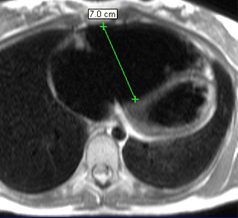

– Insuffisance aortique : recherche de bicuspidie et quantification de la fraction de régurgitation par l’IRM sont fiables.

– Rétrécissement aortique : Recherche de bicuspidie fiable, possibilité de quantification de la surface valvulaire et du gradient systolique.